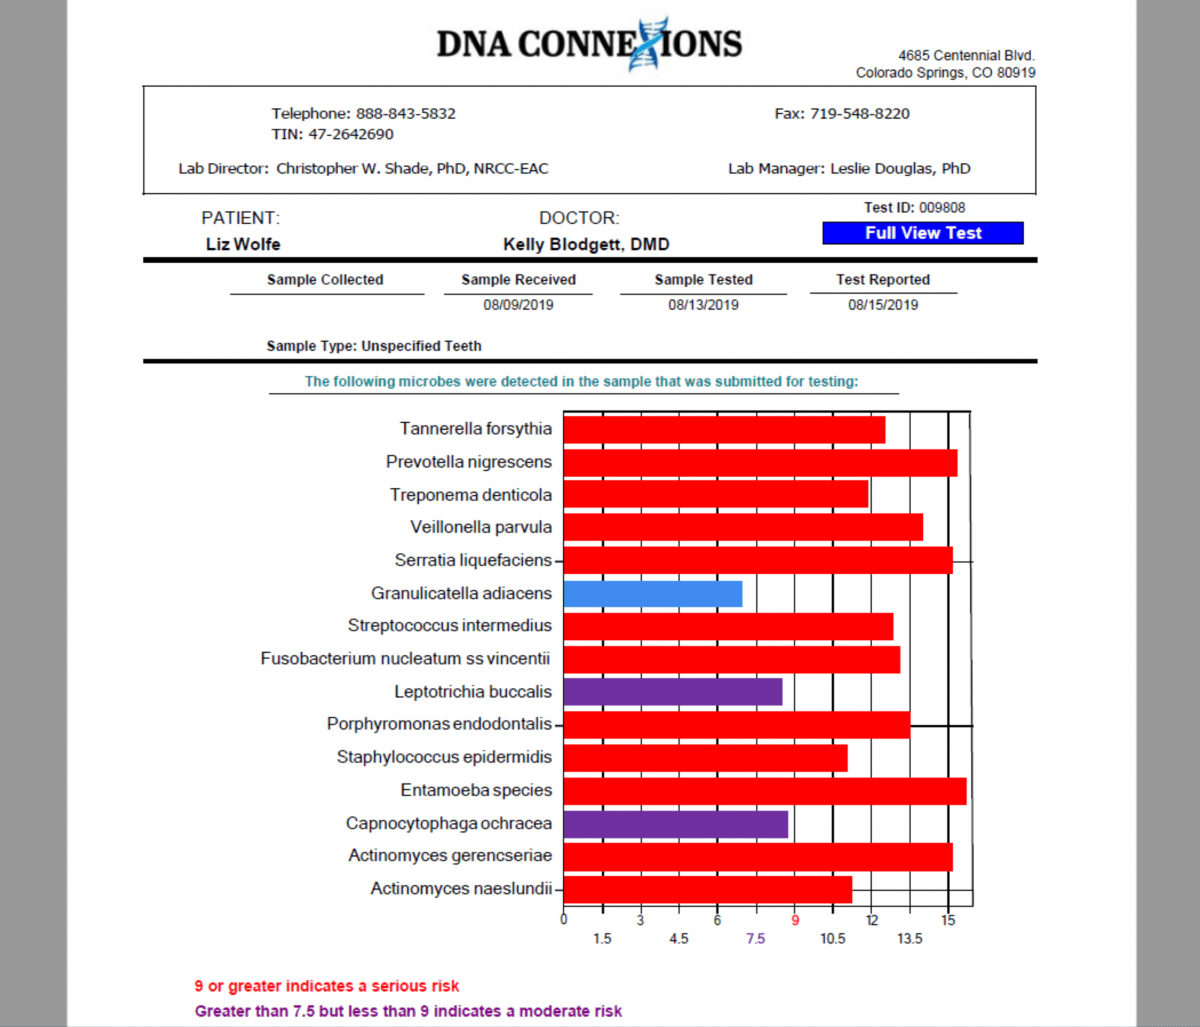

The image below illustrates the 15 pathogenic bacteria that were trapped in her dead tooth root and jawbone.